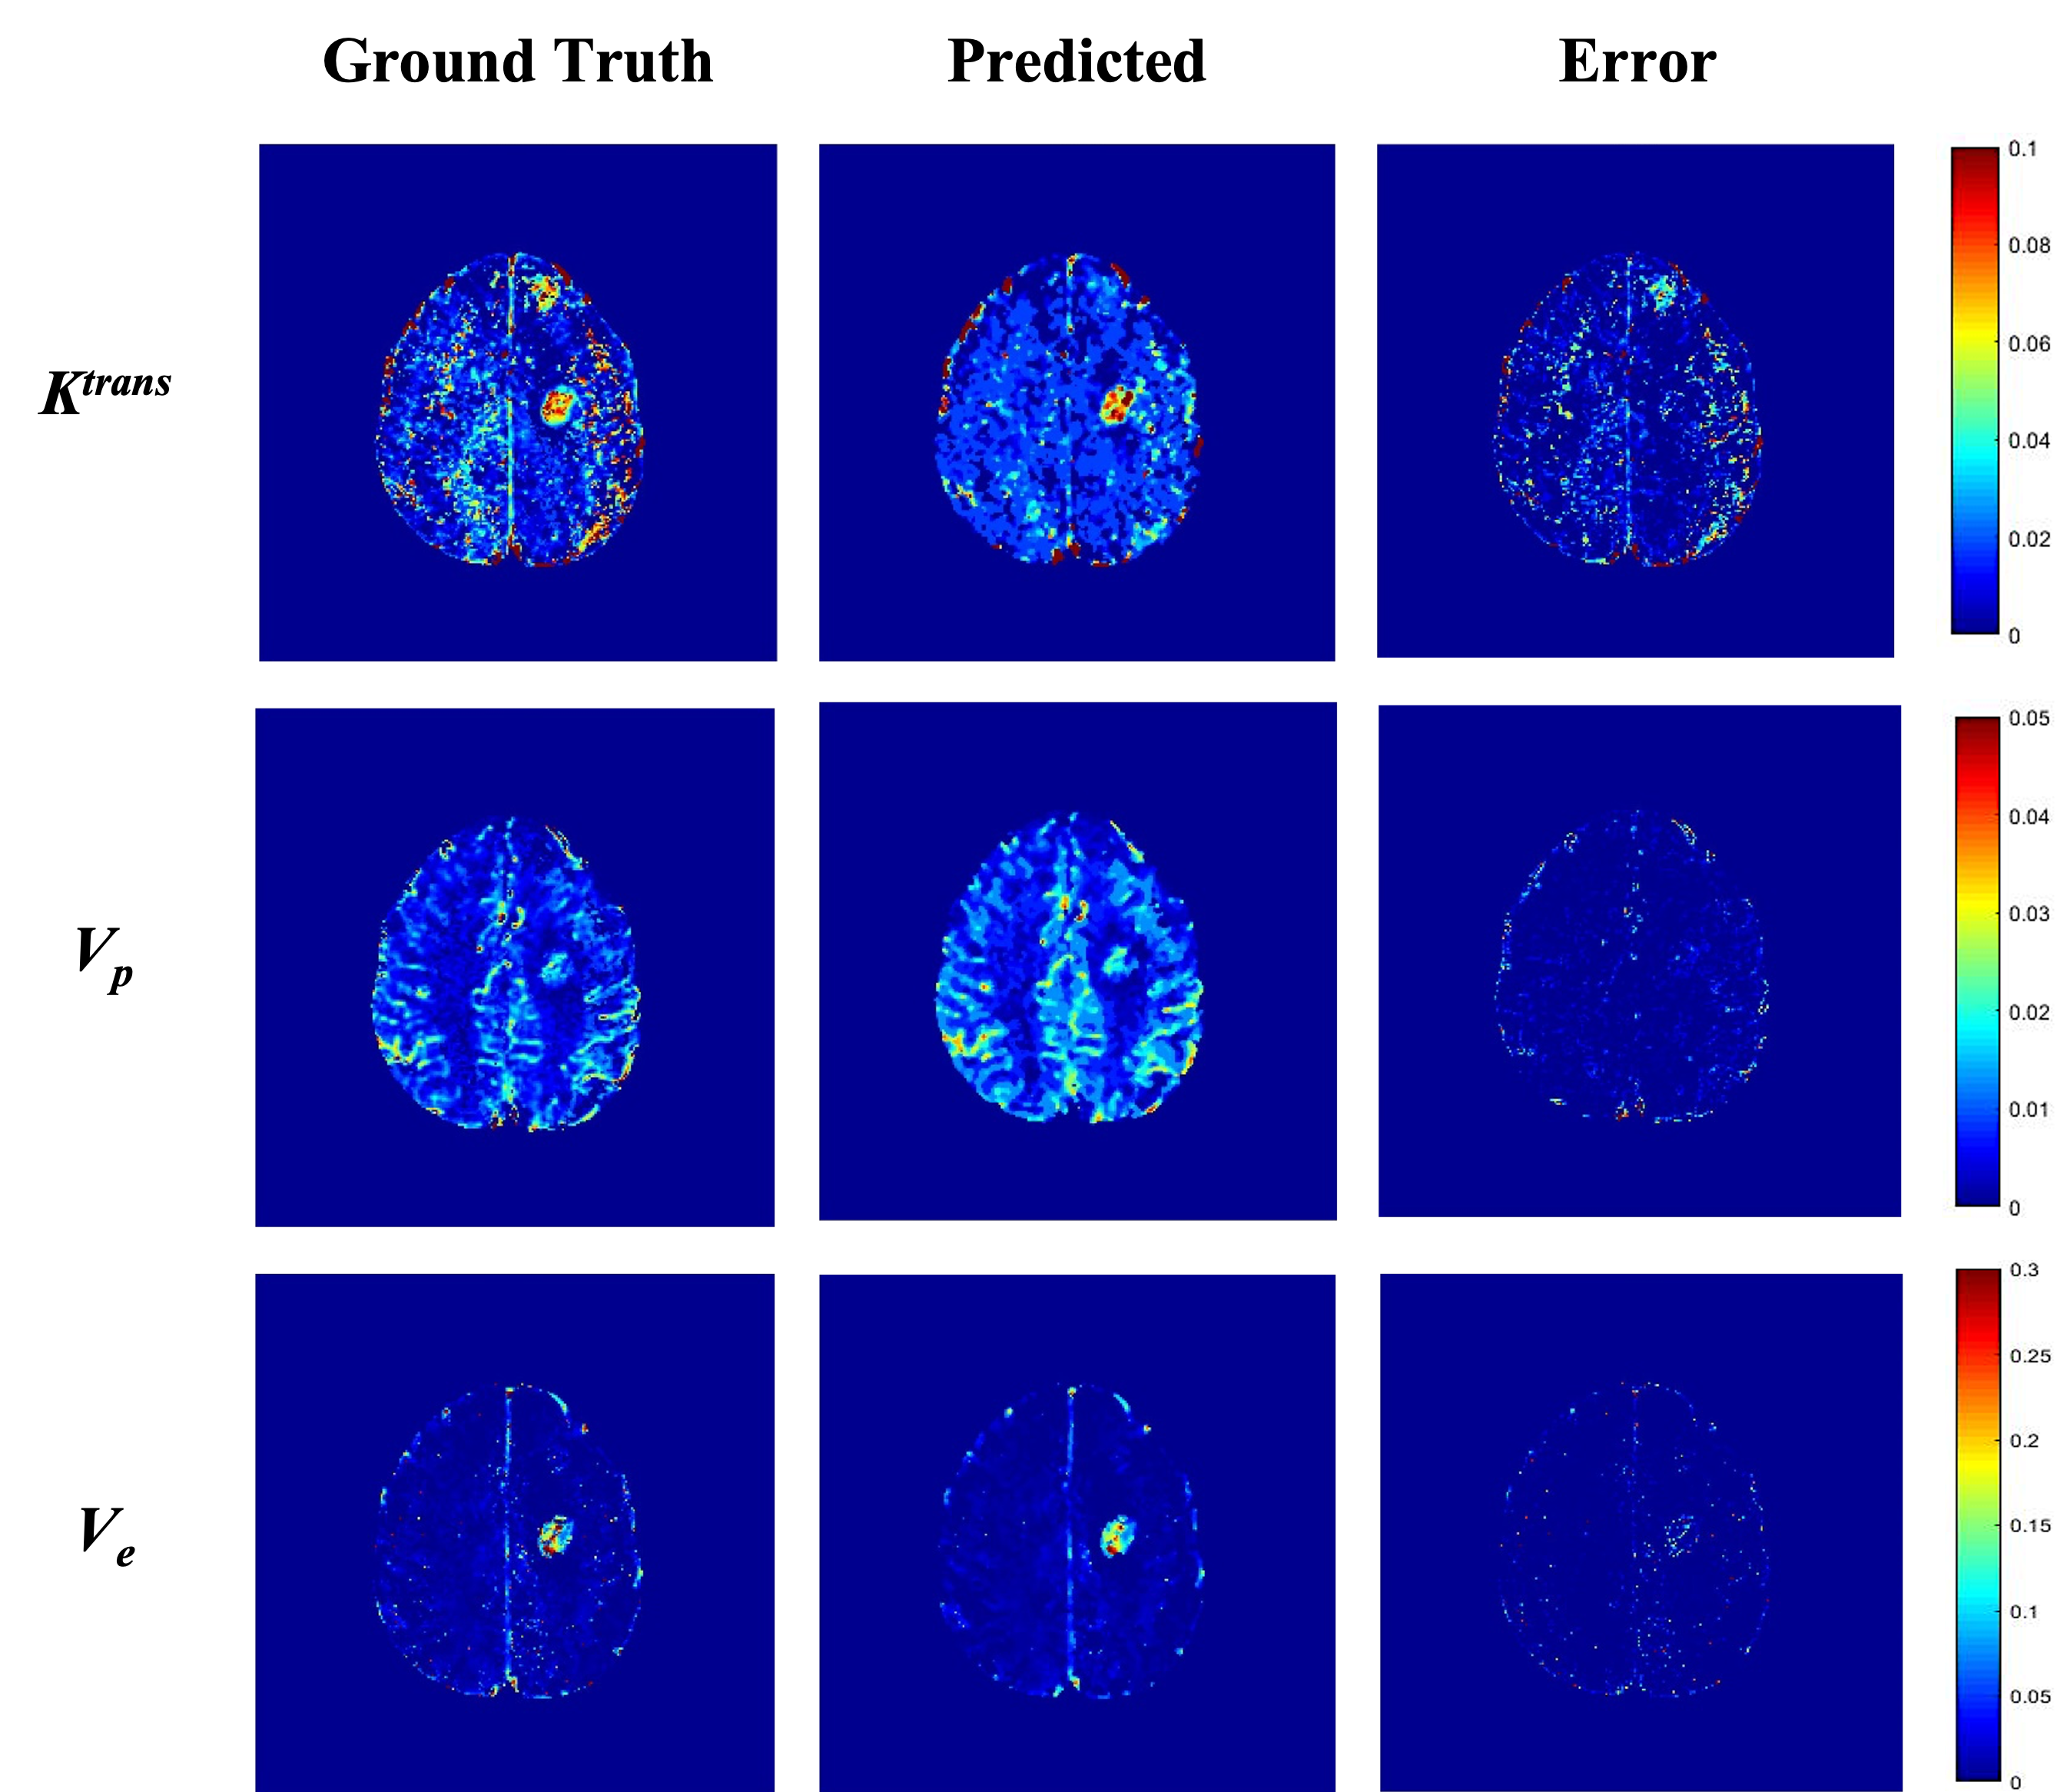

The training and testing results for synthetic data showed the best results for predicted Vp values. Similar performance was seen in patient data as well (Table 1). The maps obtained were less noisy as compared to conventional ones (Figure 2). The processing time was reduced from 77 min to 5.3 min to process one patient data on Intel Xenon(R), 64 GB Ram, Nvidia Quadro K600.

Figure 2: TK Parametric maps: each row shows ground truth, predicted and error maps of Ktrans, Vp & Ve respectively of a representative case of Brain Tumor